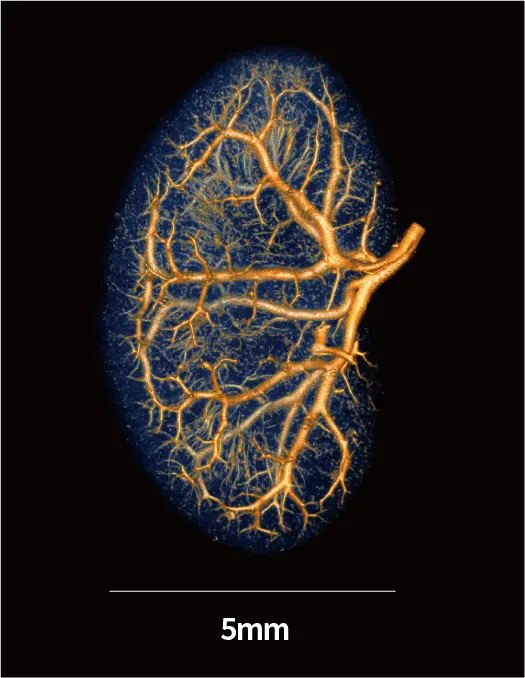

Microfil造影剂对离体小鼠肾脏进行精准灌注,使造影剂充分充盈肾血管网络与实质结构后,使用IMAGING 100进行超高分辨率扫描和重建。结果显示:肾脏三维轮廓完整饱满,全肾血管树清晰连贯,细微血管分支清晰可辨,组织结构对比度极佳。

▲超高分辨率·离活一体Micro-CT(型号:IMAGING 100)